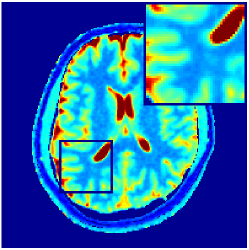

Two sets of experiments were conducted here: first, we used the 2D and 3D acquisition sequences for scanning a healthy volunteer’s brain (real-world acquisitions). Figures 6 and 7 display the parametric maps reconstructed from 2D spiral and radial readouts. We computed the T1, T2 and proton density (PD) maps using baseline reconstruction algorithms ZF, VS, LR, FLOR, AIR-MRF and our proposed LRTV. While baselines use DM either for quantitative inference or also during reconstruction (i.e. AIR-MRF), we further compare the DM-free LRTV’s performance when cascaded to DM, KM and MRFResnet for quantitative inference. For the 3D spiral acquisitions we compared LRTV and its closest competitor VS in Figure 8. Outcomes from other tested algorithm are displayed in the supplementary materials (Figure S5). Since FLOR does not use dimensionality-reduction, our system ran out of memory during 3D reconstruction; hence results are not reported in this case.

VI-E1 Discussion

The LRTV-DM and LRTV-MRFResnet perform on par, and both outperform all tested baselines for reconstructing T1, T2 and PD maps in all acquisition schemes. This can be observed both visually in Figures 6, 7, 8, S2 and S3, and quantitatively in Table IV across all tested metrics. Other baselines were unable to successfully remove the under-sampling artefacts in TSMIs, and these errors propagated to the parameter inference phase and resulted in inaccurate maps. Temporal-only priors incorporated within LR are shown insufficient to regularise the inverse problem and LR sometimes (e.g. 2D spiral acquisitions) can admit solutions with even stronger artefacts than the model-free ZF baseline. This issue was previously studied for other non-Cartesian MRF readouts that similar to our spiral/radial trajectories, miss to sample the corners of the k-space in all timeframes (see section 2.2.2 and figure 2 in [19]). In the absence of reference for the k-space corners information, the LR iterations despite minimising the objective can converge to solutions with high-frequency artefacts, as visible in the computed maps. This highlights the need for adding an appropriate spatial-domain regularisation. FLOR reduces the LR’s artefacts but this improvement is limited because the suggested nuclear norm penalty does not incorporate an explicit spatial regularisation. Further for reducing artefacts, FLOR can introduce an undesirable bias in the computed T1/T2 maps e.g. see error maps in Figures S2 and S3. The non model-based VS baseline incorporates spatial regularisation and results in spatially smoother maps than ZF and LR, but it is unable to output artefact-free images. Further and consistent with our in-vitro experiment, we observe that VS overestimates the T2 values (e.g. in White and Grey matter regions) in tested 2D acquisitions i.e. the spatial regularisation trades off agains the quantification accuracy. The model-based AIR-MRF adds spatial regularisation through 2D/3D low-pass Gaussian filters however this trades off the sharpness of the computed maps and can increase the errors at the tissue boundaries (we searched Gaussian spreads that keep the blurs and high-frequency artefacts minimal). For our acquisition readouts, Gaussian filters performed better than disk filters of [19] for avoiding strong Gibbs artefacts. On the other hand, the spatiotemporally regularised LRTV greatly improves the TSMI reconstructions i.e. 4 dB enhancement compared to the closest competitor baseline (Table IV). This enables computing accurate and aliased-free multi-parametric inference using DM or the DM-free learning-based alternative MRFResnet as visible in Figures 6, 7, 8, S2 and S3. MRResnet and DM score competitive quantitative inference results i.e. T1 and T2 MAPE less than 5% and 9%, respectively (Table IV). KM also outputs comparably accurate T1 maps, however this shallow learning model despite having a model size larger than MRFResnet, is unable to learn accurate T2/PD quantification and it results in poor estimated maps, consistent with our observations in section VI-C.